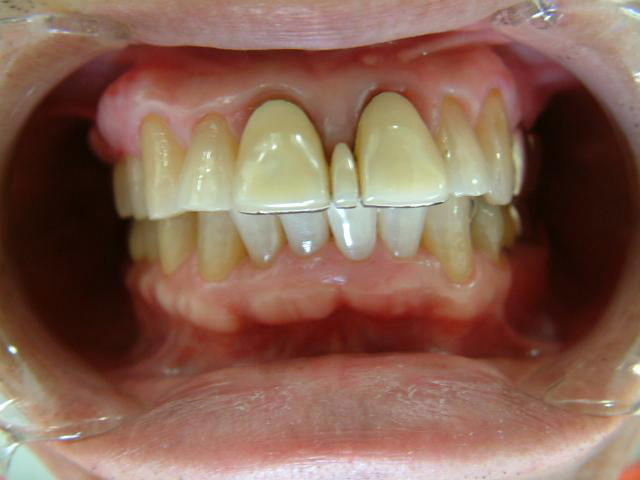

下顎前歯切端を内側に削って頂いた所 |

補綴物物 完成

患者さんから「出っ歯にならないよに!」

と再度念を押されたので

出来る限り内側に入れて製作しました。

模型上では、1.1下部孤形空隙が広いように

見えますが、歯肉模型にて調整して

歯肉を圧迫せず、息が漏れることが無いように

調整しました |